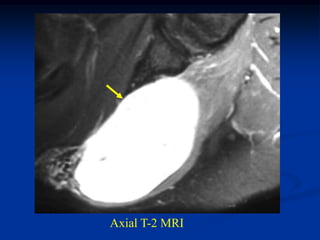

Case # 260                   Axial T-1 MRI

67 year male with subcutaneous MFH thigh

Axial T-2 MRI

Sagittal T-2 MRI